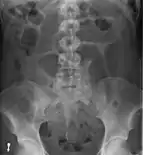

Coffee bean sign in a person with sigmoid volvulus

An x-ray of a person with a small bowel volvulus.

Plain X ray of a cecal volvulus